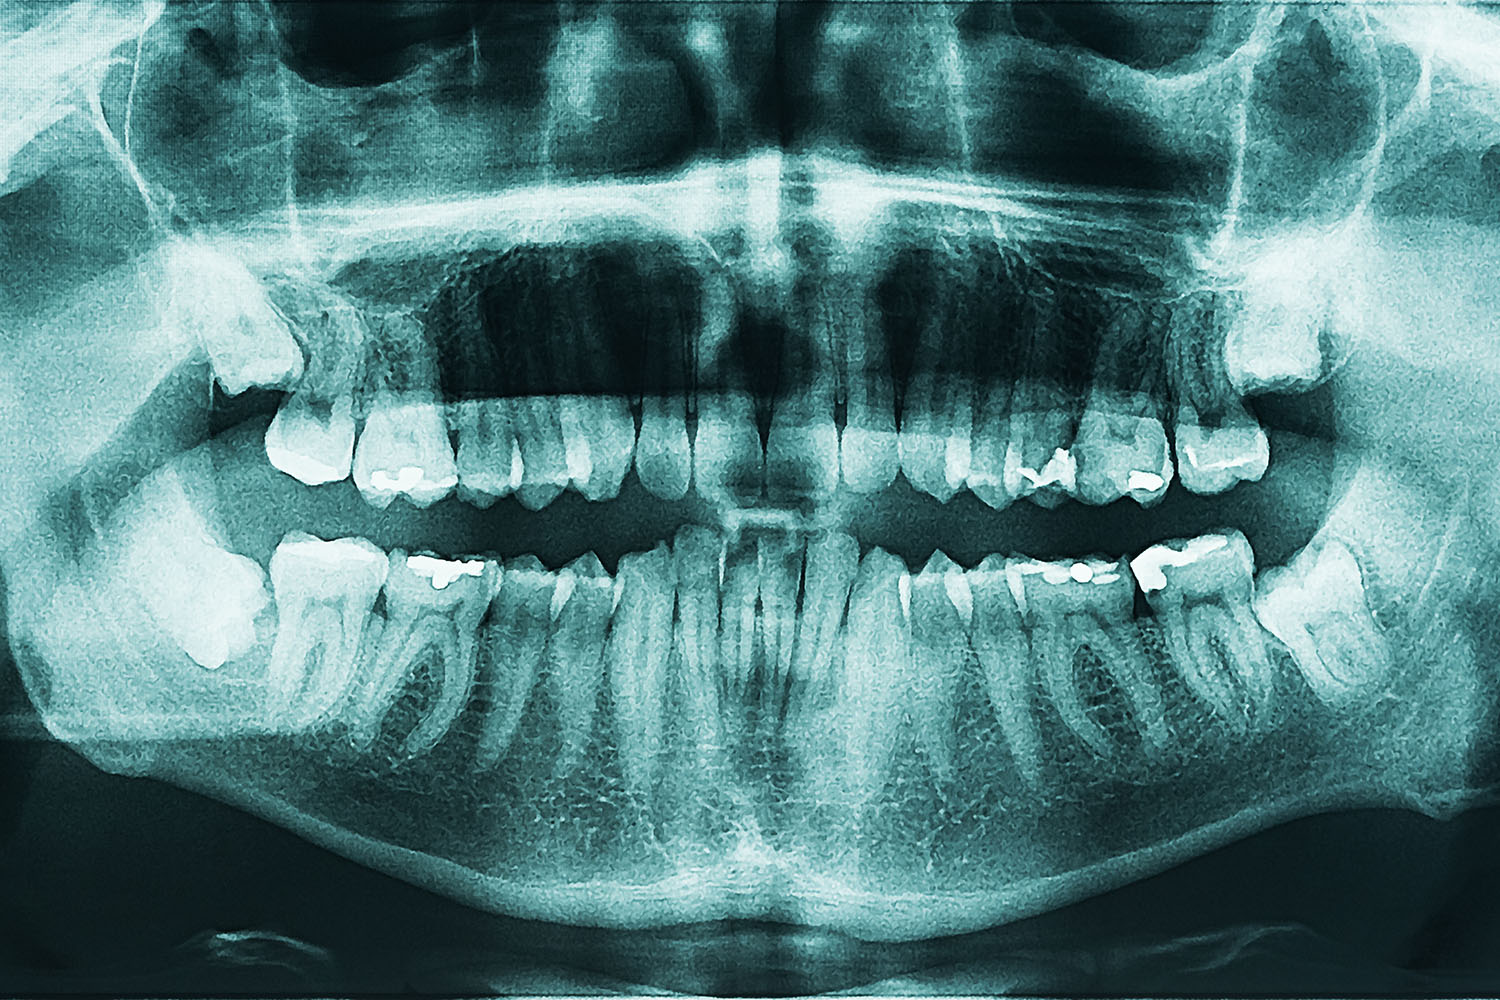

レントゲン検査

歯の根や顎の骨の状態を詳しく確認するために、レントゲン撮影を行います。

目に見えない歯や骨の状態までしっかり確認することで、より安全で的確な治療につなげられます。